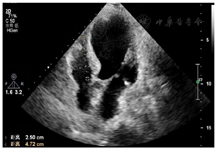

患者,女性,84岁,因"反复胸痛1周,持续加重8 h"于2021年8月17日急诊收治入院。既往无高血压、糖尿病病史。入院查体:血压105/56 mmHg(1 mmHg=0.133 kPa),神清,气略促,对答切题,颈软,颈静脉无怒张,双肺呼吸音粗可闻及较多的湿啰音,心率112次/min,律齐,各瓣膜区未闻及病理性杂音,腹平软,无压痛,反跳痛,肝脾肋下未及。双下肢轻度浮肿,四肢肌力正常,病理征(-);急诊心电图示:急性广泛前壁心肌梗死(图1);胸部CT提示双侧间质性肺水肿可能(图2);实验室检查:肌钙蛋白T:3.13 μg/L,肌酸激酶同工酶:188.93 μg/L,D二聚体:1.36 mg/L。根据患者病史、心电图及心肌酶学明确诊断为急性ST抬高型心肌梗死,予以术前嚼服负荷量绿色通道行急诊再灌注治疗,冠脉造影示:前降支次全闭塞,远端TIMI血流0级,回旋支近端40%~50%局限性狭窄,TIMI血流3级,右冠起源左冠窦,无狭窄,TIMI血流3级,于前降支近端植入3.0 mm×18 mm Firebird 2支架一枚(附件冠脉造影+PCI图3、视频1)后安返CCU。继续予以心电及血流动力学监测,动态监测心电图及酶学改变,阿司匹林、替格瑞洛抗血小板聚集,他汀调脂、稳定斑块,扩管利尿改善心功能等治疗。3 h后患者突发血压下降为60/40 mmHg,四肢湿冷,动脉搏动弱,意识尚清,指末氧饱和度95%,心电监测提示窦性心动过速,心率130次/min。立即予以平衡液扩容,多巴胺+去甲肾上腺素提升血压,留置颈内静脉置管监测CVP,股动脉置管监测有创动脉压。床旁心超提示微量心包积液,右房室内径偏小(37 mm×18 mm,40 mm×22 mm),左室壁多壁段运动异常,EF35%(图4),床位医师考虑容量不足,继续补液扩容及血管活性药物升压,但患者血压仍未见回升;再次复查心超提示心包积液较前明显增多,未见室壁不连续及异常血流信号,考虑心包填塞(图5),立即行心超定位剑突下心包穿刺,引流出暗红色不凝血,予以心包置管留置引流出血性液体300 ml,患者血压恢复至119/49 mmHg,心率95次/min,再次复查心超示左室心尖处见几束细丝状异常血流信号局限于纤维膜状回声内,考虑左室心尖破裂伴假性室壁瘤可能性大(图6)

出院前复查心超:左室壁破裂修补术后,左室壁节段性运动异常伴心尖部室壁瘤形成,EF34%,微量心包积液(图7)。